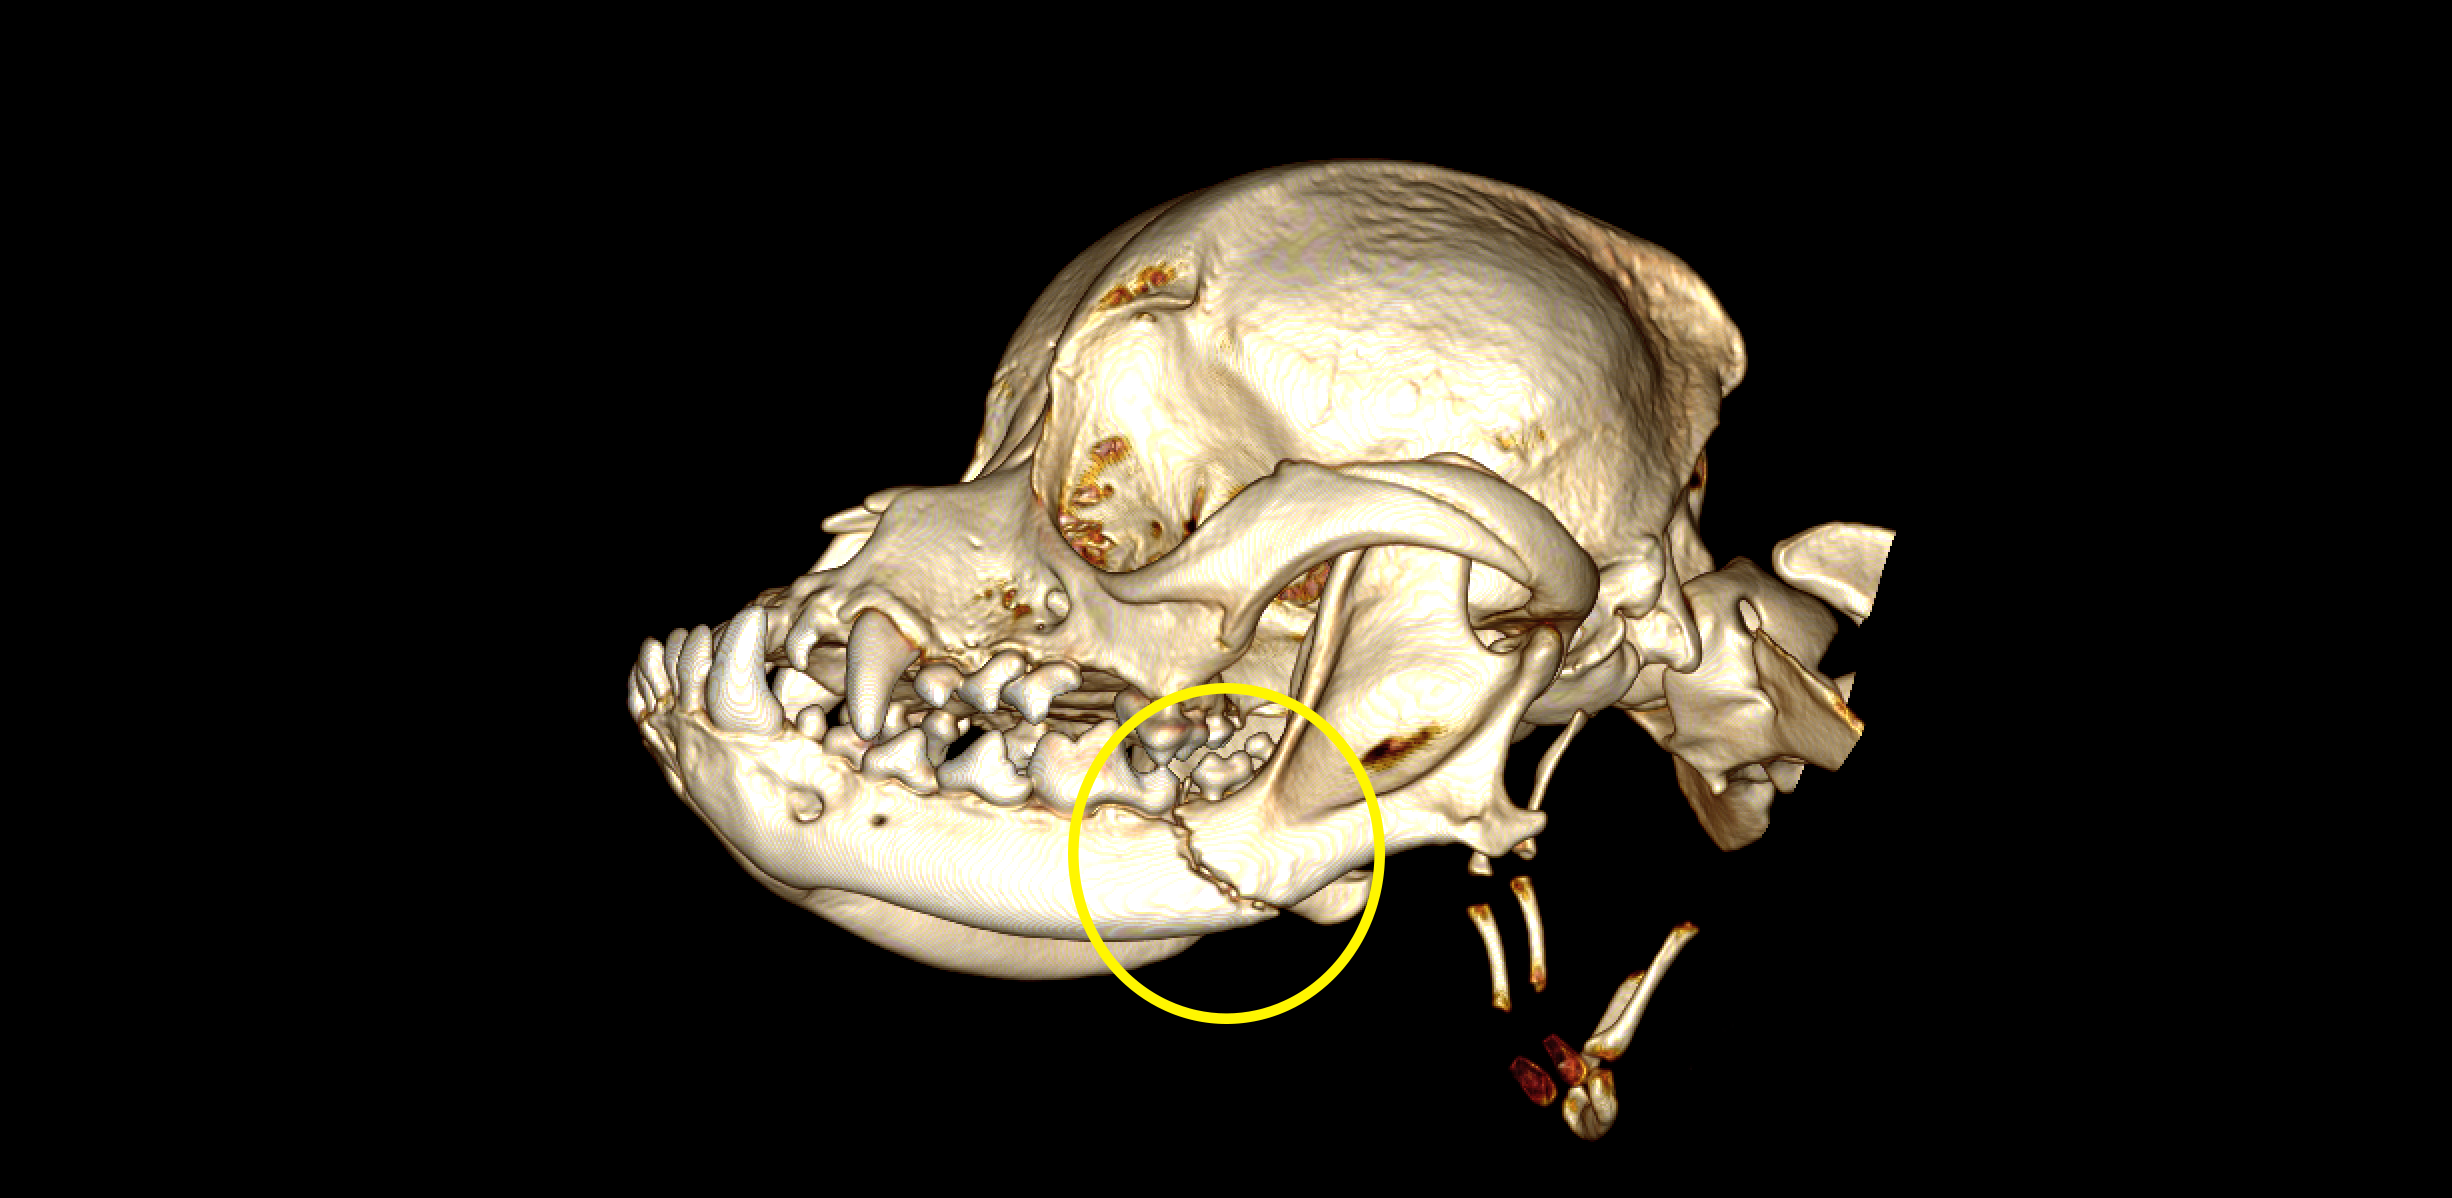

Standiford Veterinary Center strives to provide our patients with the highest level of care. One of the many advanced medical services provided is Computed Tomography or CT scan. CT takes numerous thin “slices” (or X-rays) of the area of interest and then reconstructs the data mathematically into a highly sophisticated and detailed 3-D representation. This scan can be rotated allowing the bones, soft tissue, and vascular structures to be isolated and individually evaluated. Contrast media can be included to markedly improve imaging accuracy and sensitivity.

Most patients are referred for advanced CT imaging when routine diagnostics such as ultrasound or radiographs cannot accurately provide the information needed for a diagnosis or prognosis. CT is exceptional in detecting changes in bones, joints, and cavities or sinuses in the head including the inner ear. The CT also visualizes the spine, chest, lungs, and abdomen. Again contrast agents can provide a detailed map of the blood flow to particular areas such as the liver.